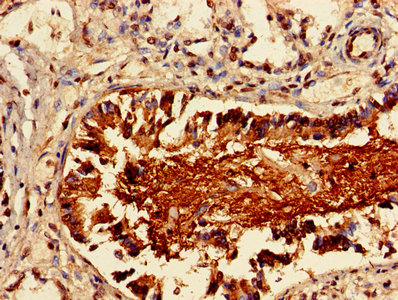

Immunohistochemistry of paraffin-embedded human appendix tissue using CSB-PA012721LA01HU at dilution of 1:100